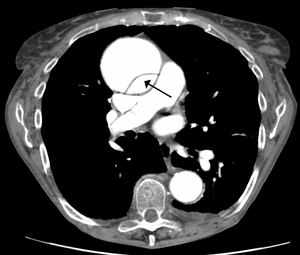

- CT aortogram chest

- Study of choice

- Similar sensitivity/specificity to TEE and MRA